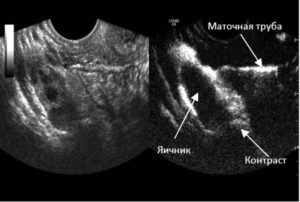

- Врач вводит тонкий катетер в полость матки через ее шейку. После чего в орган подается стерильный физраствор температурой в 37 градусов (или Эховист).

- Под контролем УЗИ врач наблюдает за процессом заполнения раствором матки и фаллопиевых труб.

Процедура проходит под контролем УЗИ. Пациентку укладывают на гинекологическое кресло, ноги согнуты в коленях. Во влагалище вводится гинекологическое зеркало. Затем обрабатывают шейку матки и влагалище антисептиками. Через цервикальный канал шейки матки в маточную полость вводят катетер.

Следующим этапом станет введение в полость матки физраствора. Жидкость попадёт сначала вовнутрь матки, а затем пройдёт по маточным трубам. Именно процесс прохождения жидкости по трубам и отслеживают с помощью УЗИ. Сама процедура длится примерно 25-30 минут, УЗИ – контроль может осуществляться трансабдоминально и трансвагинально.

УЗИ ГСГ маточных труб проводят приблизительно на пятый – десятый день менструации. В матку вставляется катетер, через который вводят контрастное вещество. Этот препарат поступает и в трубы. Это улучшает их визуализацию.

Таким образом врач может осмотреть особенности строения труб. Контраст продолжает вводиться и далее поступает в полость брюшины. Это указывает на хорошую проходимость труб.

- Через катетер пропускают стерильный физиологический раствор. Он продвигается вдоль по маточным трубам.

- На экране УЗИ-аппарата подсвечивается область протекания физраствора. Там, где раствор остановился, фиксируют спаечный процесс.

В результате сонолог может увидеть гидросальпинкс, скопление транссудата на УЗИ с полипами и миоматозными узлами. Диагностируются перечисленные патологии, если раствор из катетера не проникает в брюшную полость, а скапливается. Так определяется отрезок непроходимости в маточных трубах.

В норме физиологический раствор из катетера проходит по маточным трубам. В некоторых случаях после проведения ультразвуковой гистеросальпингоскопии наступает долгожданная беременность.